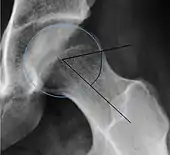

Projectional radiography ("X-ray")is often considered first line for FAI.[10] Anterior-posterior pelvis and a lateral image of the hip in question should be attained.[10] A 45-degree Dunn view is also recommended.[10][19]

Alpha angle | ![]() |

Degree of bulging of the femoral head-neck junction: In normal conditions there is a symmetric concave contour at the junction of the femoral head and neck. Loss of this concavity or bone bulging may lead to cam type impingement. The degree of this deformity can be measured by the alpha angle. Although it can be measured in the cross-lateral view, the 45° Dunn view is considered more sensitive and the frog leg view more specific in determining pathologic values. |

|